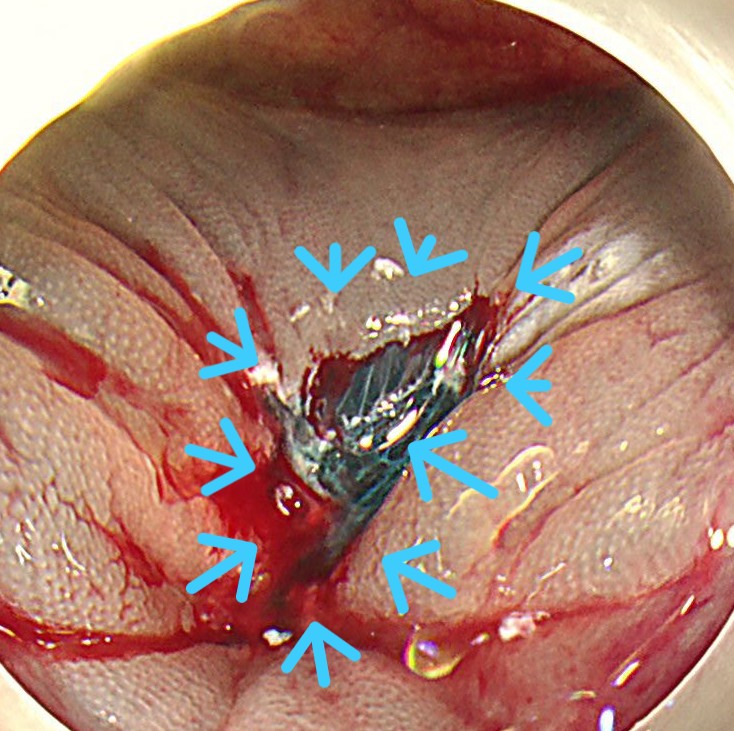

切除断端はクリップ閉鎖します。病理学的に根治切除と診断されました。